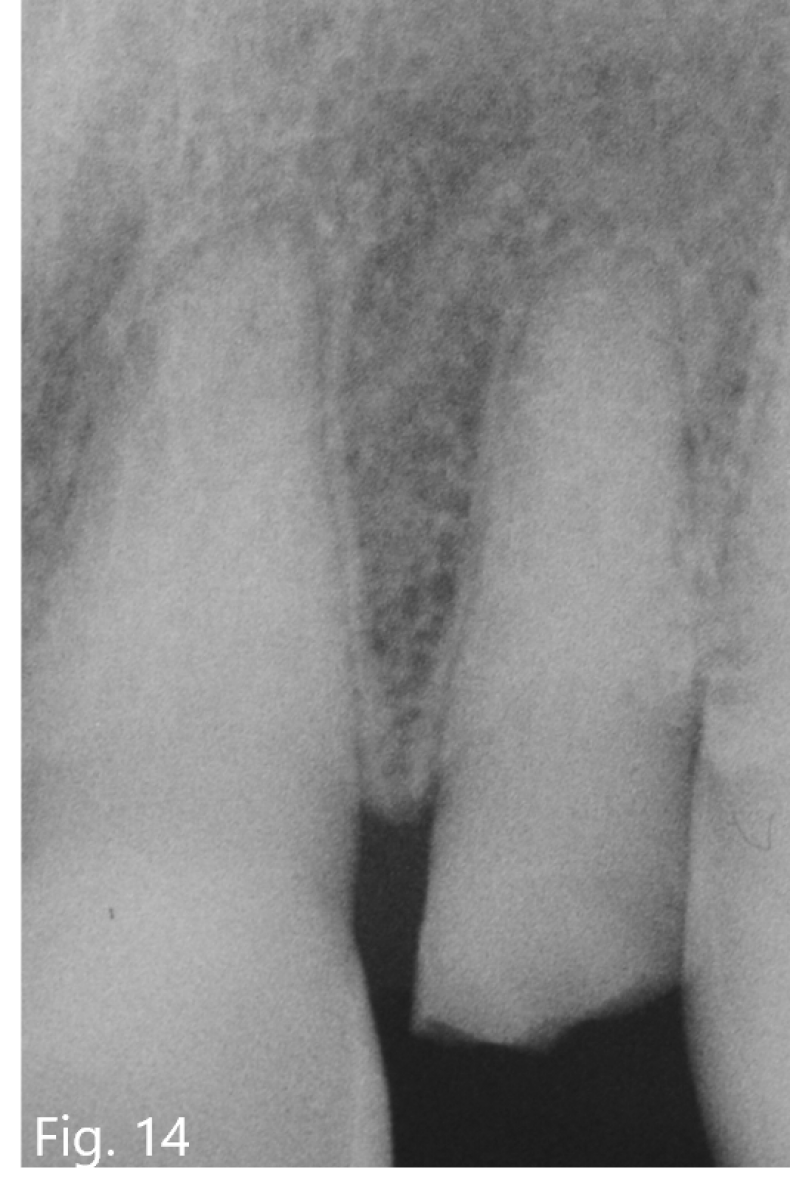

A 50 years old patient came to our office because of an emergency: while eating he broke the tooth 2.2 and he was not able to find the fragment (Fig. 13).

The fracture had exposed the pulp and the patient referred spontaneous and acute pain. The pre-operative x-ray showed that the tooth had a very thin canal lumen (Fig. 14) and a sufficient bone support, then it was decided to do an endodontic treatment followed by restoration and prosthetic crown.